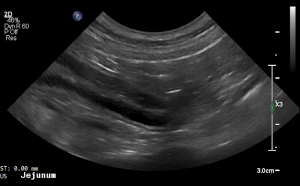

SIMON Ultrasound Database

This ultrasound database is a free resource for students and doctors!

Our collection includes videos of dogs, cats, horses, cows, humans, and many other species!

–Canine and Feline abdominal ultrasound videos were generously provided by the Cummings School of Veterinary Medicine at Tufts University.